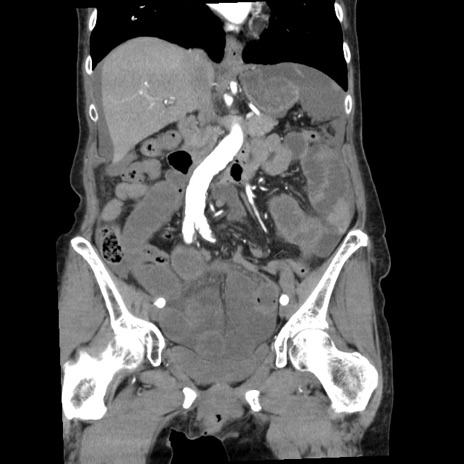

横断像

【症例】80歳代女性

【主訴】腹痛

【現病歴】8時間前から腹痛あり来院。

【既往歴】糖尿病、脂質異常症、子宮体癌にて子宮全摘術

【身体所見】意識清明・会話良好だが腹痛で苦悶様、全腹部にわたって反跳痛と圧痛あり

【データ】WBC 13600、CRP 0.14、LDH 224、CK 90